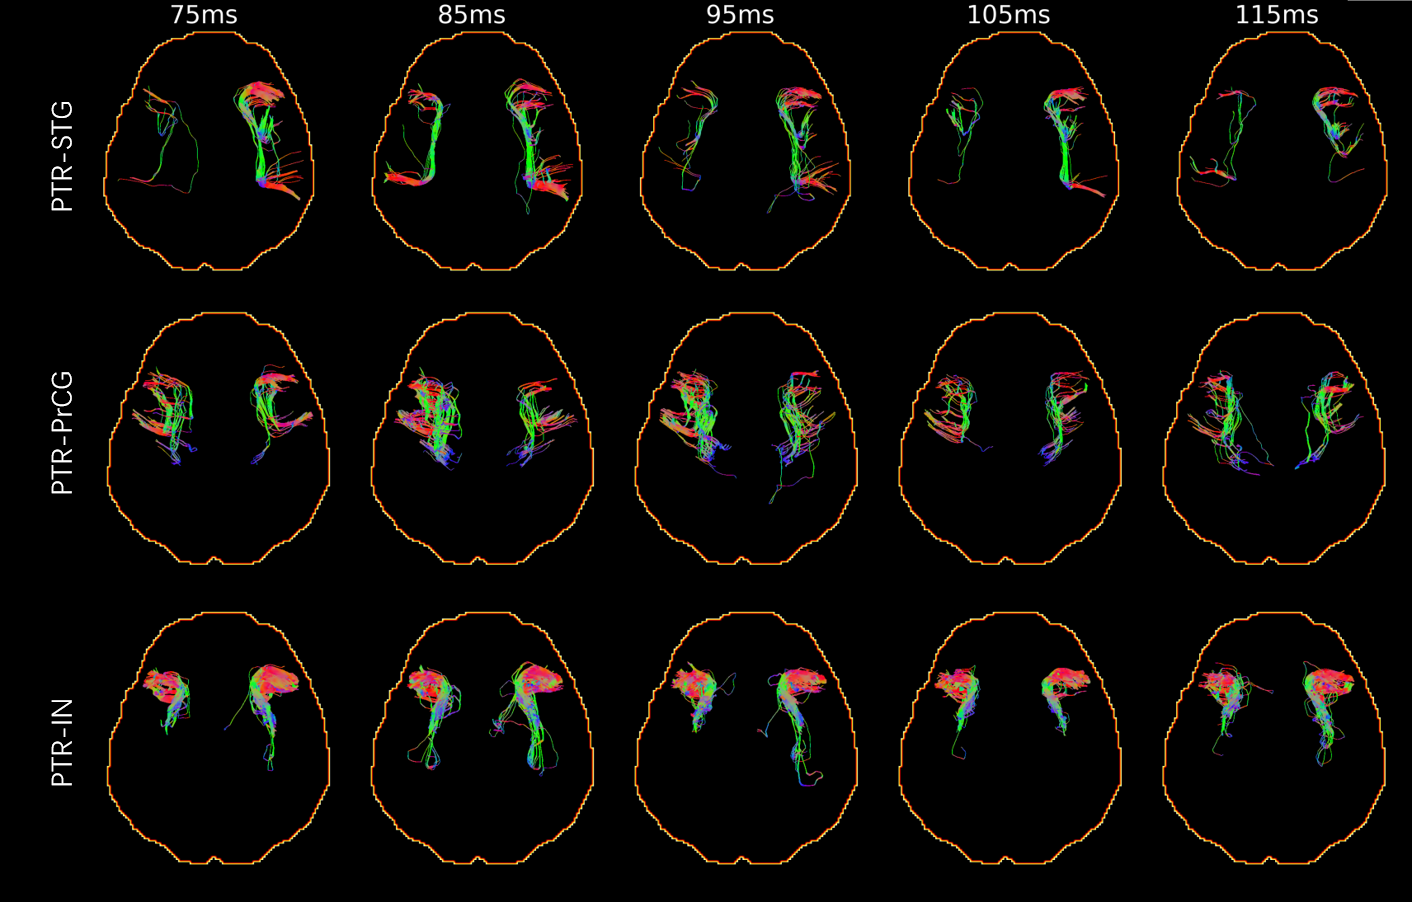

Detailed Connectomic Cluster Resource for White Matter Mapping From Ultra-High-Field Diffusion MRI

Hiuying Yip, Yifei He, Yu Xie, Fan Zhang, Ye Wu

NeuroImage, 2026

Demonstration of TE-dependence of lateralization of structural connectomes

Yifei He, Xiaoming Liu, Peng Sun, Tenglong Wang, Yizhe Zhang, Jiaolong Qin, Tao Zhou, Ye Wu

Annual Meeting of the International Society for Magnetic Resonance in Medicine (ISMRM), 2024